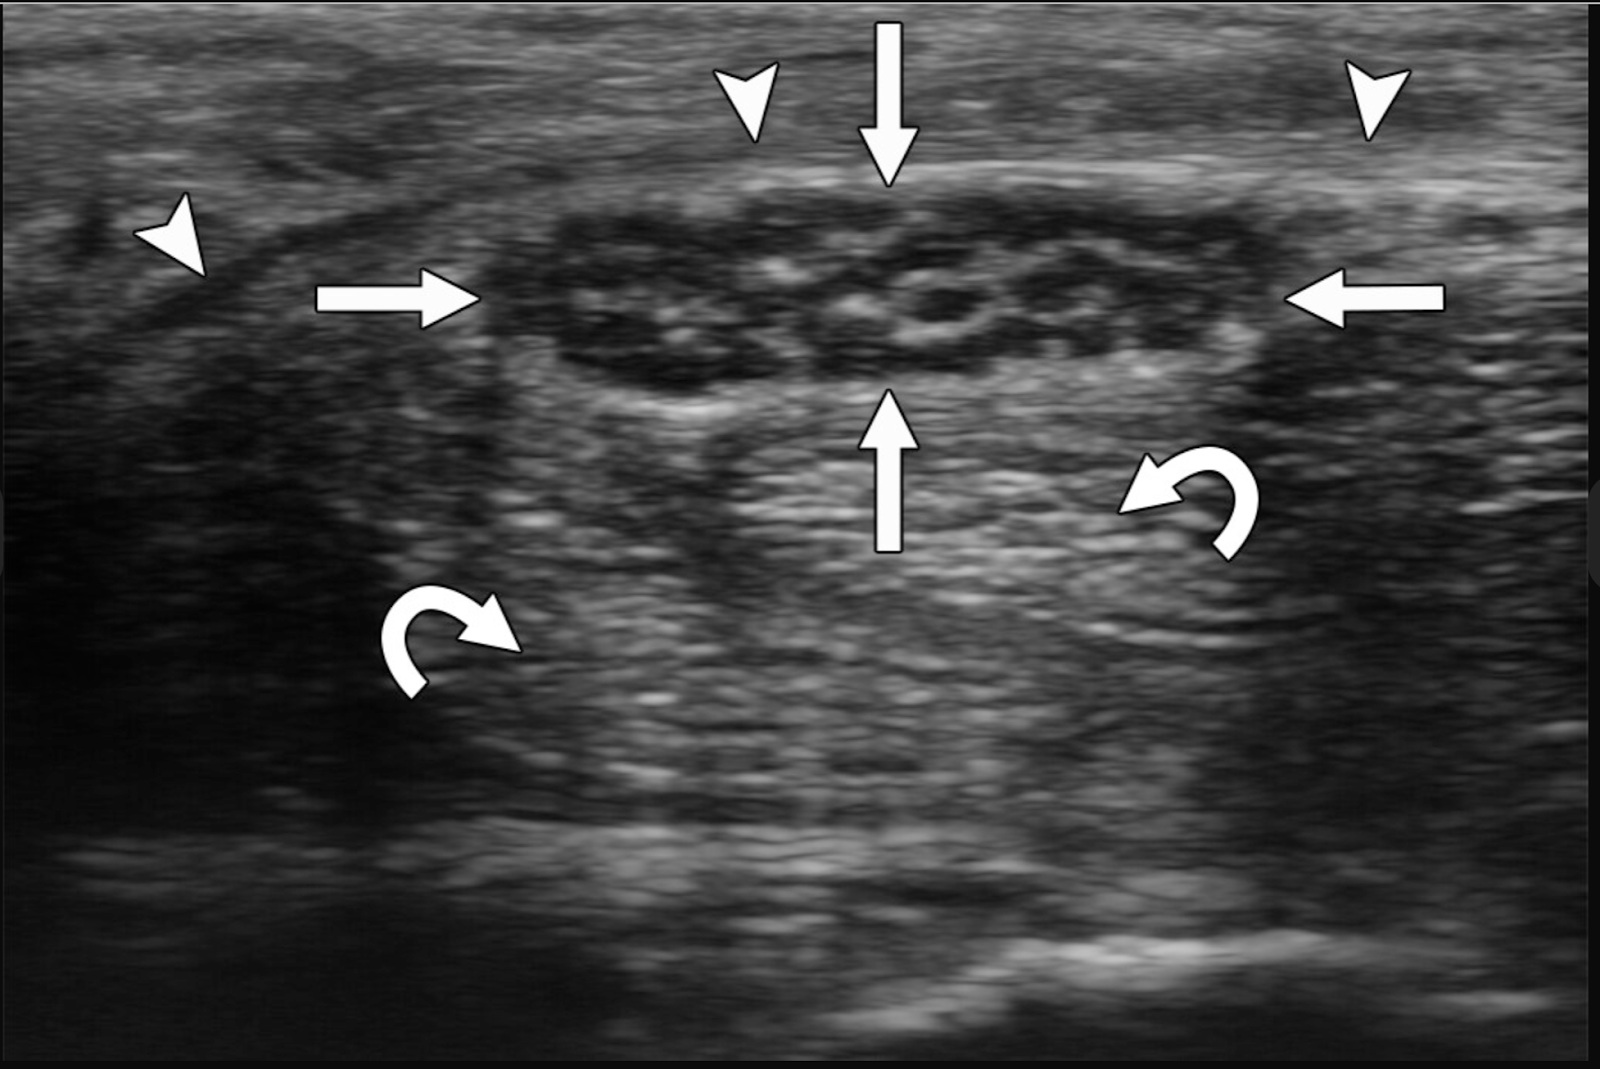

Imagem de ultrassom obtida usando transdutor de alta frequencia mostra seção transversal da polia A1 normal ( setas retas ) restringindo tendões flexores superficialis mais profundos (Sup) e profundus (Prof) sobre a falange proximal. Os tendões flexores não são bem visualizados devido à anisotropia. A anisotropia também é vista onde a polia A1 se curva ( setas curvas ) em ambos os lados dos tendões flexores.

Imagem de ultrassom obtida usando transdutor de alta frequencia mostra seção transversal da polia A1 ( setas ) surgindo da falange proximal e restringindo os tendões flexores superficialis (Sup) e profundus (Prof) adjacentes.